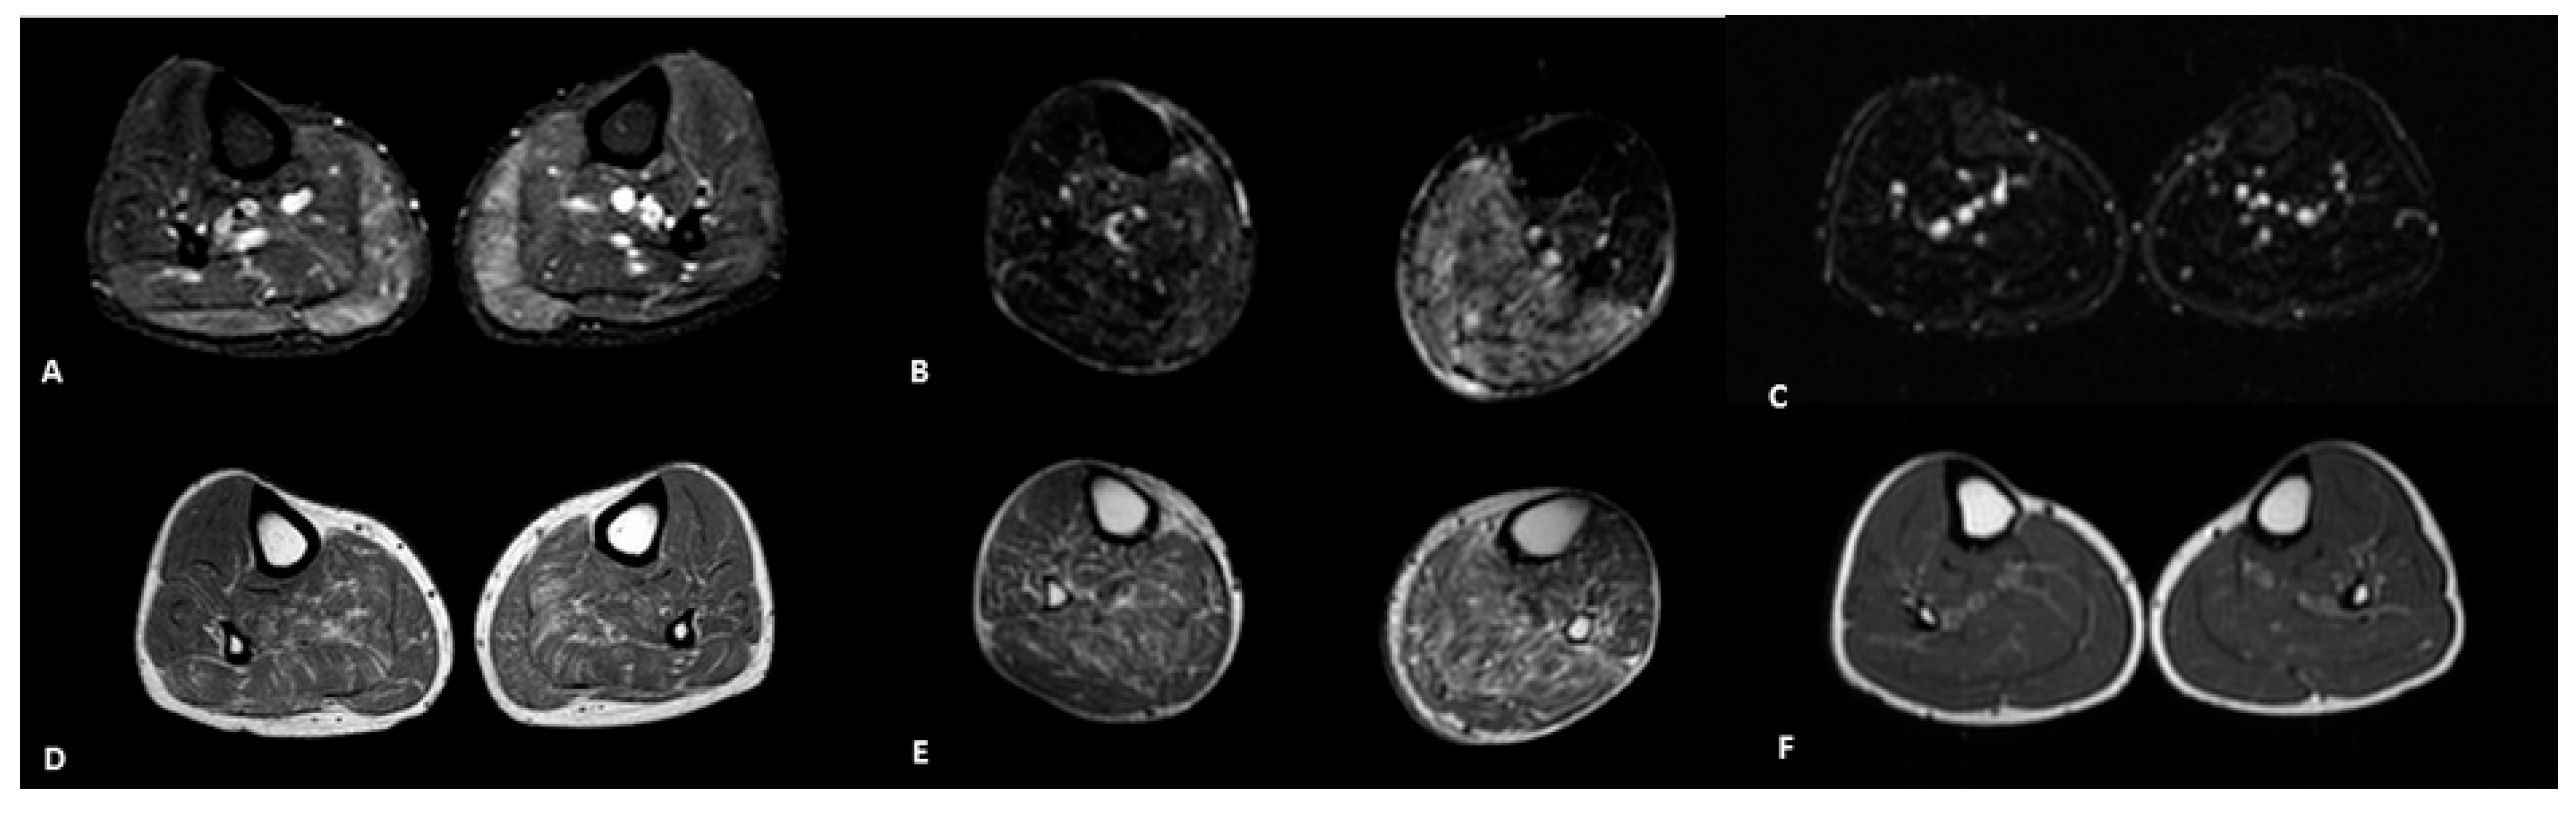

3. Results